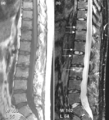

thumb|[[Magnetic resonance imaging|Magnetic resonance images of the fingers in psoriatic arthritis. Shown are T1-weighted (a) pre-contrast and (b) post-contrast coronal images. Enhancement of the synovial membrane at the third and fourth proximal interphalangeal (PIP) and distal interphalangeal (DIP) joints is seen, indicating active synovitis (inflammation of the synovial membrane; large arrows). There is joint space narrowing with bone proliferation at the third PIP joint and erosions are present at the fourth DIP joint (white circle). Extracapsular enhancement (small arrows) is seen medial to the third and fourth PIP joints, indicating probable enthesitis (inflammation of a tendon insertion).]] thumb|[[Sagittal plane|Sagittal magnetic resonance images of the ankle region in psoriatic arthritis. (a) Short tau inversion recovery (STIR) image, showing high signal intensity at the Achilles tendon insertion (enthesitis, thick arrow) and in the synovium of the ankle joint (synovitis, long thin arrow). Bone marrow edema is seen at the tendon insertion (short thin arrow). (b, c) T1 weighted images of a different section of the same patient, before (panel b) and after (panel c) intravenous contrast injection, confirm inflammation (large arrow) at the enthesis and reveal bone erosion at tendon insertion (short thin arrows).]] There is no definitive test to diagnose psoriatic arthritis. Symptoms of psoriatic arthritis may closely resemble other diseases, including rheumatoid arthritis. A rheumatologist (a physician specializing in autoimmune diseases) may use physical examinations, health history, blood tests and x-rays to accurately diagnose psoriatic arthritis.

(a) T1-weighted and (b) short tau inversion recovery (STIR) magnetic resonance images of lumbar and lower thoracic spine in psoriatic arthritis. Signs of active inflammation are seen at several levels (arrows). In particular, anterior spondylitis is seen at level L1/L2 and an inflammatory Andersson lesion at the upper vertebral endplate of L3.